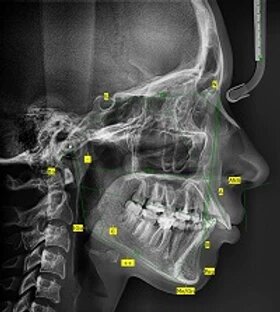

ТРГ- телерентгенограмма, стандартный 2-х мерный рентгеновский снимок, назначаемый в основном стоматологами-ортопедами, челюстно-лицевыми хирургами и травматологами.

Снимок можно произвести в двух основных проекциях, прямой и боковой, в зависимости от того, что именно хочет увидеть врач. На снимке ТРГ можно увидеть не только костную, но и мягкие ткани, что позволяет лучше составить программу лечения в ортодонтии. Для чего нужен снимок ТРГ: - определить правильность расположения верхней и нижней челюсти - определить наклон зубов относительно основания черепа

- оценить мягкие и костные ткани лица- определить наличие асимметрии лицевой части черепа - определить состояние прикуса и наличие его нарушений

Анализ и расчет ТРГ, позволяет точно произвести измерение расстояний, необходимых углов, произвести очерчивание скелетного контура и контура мягких тканей (т.к. положение зубов влияет на форму лица), позволяет смоделировать перемещение зубов. Здесь можно спланировать ход ортодонтического лечения, вычислив абсолютно точно, на сколько надо сместить тот или иной зуб, математически определить сроки лечения. Таким образом, имея на руках несколько временных снимков, можно определить эффективность проводимого лечения. Т.к. анализ и расчет ТРГ требует особой точности, выполнять его должен высококвалифицированный специалист.